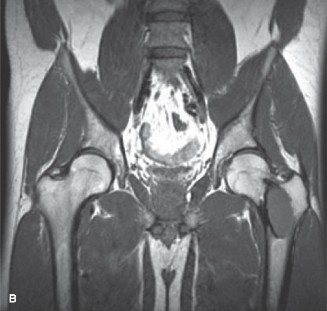

A 45-year-old male is taken to the emergency room after sustaining a motor vehicle accident. An Orthopaedic consult is placed after a unexpected finding is seen on the X-ray of his left hip. The X-rays is shown is Figure 8–40A and an MRI is shown is Figure 8–40B.

Figure 8–40 A–B

The correct answer is (D). Fibrous dysplasia is characterized by a fibro-osseous tissue within the bone and is often asymptomatic and found incidentally. Lesions can

be expansile with cortical thinning and a sclerotic rim, around central lucent lesions within the medullary canal. When it occurs in the proximal femur, a coxa vara deformity can result, termed the “shepherd’s crook” deformity.